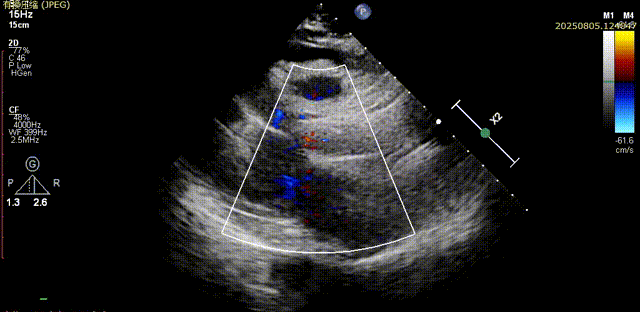

脱钩后输送器部分回收,瓣膜无位移及形变,确认瓣膜完全脱钩,回撤输送系统及导丝,超声再次评估,瓣膜位置及形态良好,无明显瓣周漏,峰值流速2.44m/s,平均压差13mmHg,患者未诉不适,入路缝合后返回病房

胸骨旁长轴评估